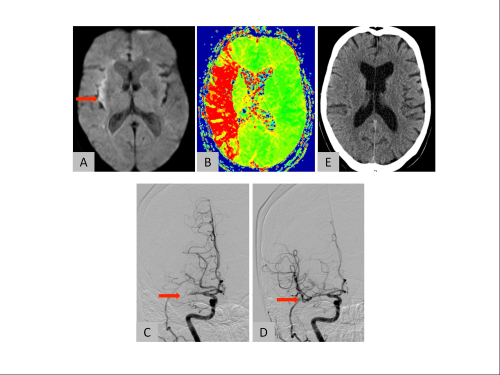

Bildgebung einer 76-jährigen Patientin mit plötzlich aufgetretener halbseitiger Lähmung links und Sehstörung. In der Kernspintomographie zeigt sich nur wenig untergegangenes Hirnge-webe (Pfeil, A) aber ein grosses Hirnareal mir unzureichender Durchblutung (rot, B).Ursache ist ein Verschluss der rechtsseitigen mittleren Hauptstammarterie des Gehirns (Pfeil, C). Der Gefässverschluss obengenannter Patientin konnte mit kathetertechnischer Therapie erfolg-reich wiedereröffnet werden (Pfeil, D). Die Patientin war am Folgetag fast beschwerdefrei und die Computertomographie zeigte nur einen kleinen Hirninfarkt (E).

Auf der Notfallstation erfolgt eine gezielte Befragung des Patienten, der Angehörigen und der Rettungssanitäter. Zudem wird der Patient körperlich untersucht, Blut wird abgenommen und ein EKG geschrieben. Es erfolgt eine Bildgebung (Computertomographie oder Magnetreso-nanztomographie, siehe Bilder) zur Darstellung des Hirninfarktes und der hirnversorgenden Gefässe und des nicht ausreichend durchbluteten Gehirns.

Eine sofortige Wiedereröffnung des verschlossenen hirnzuführenden Gefässes ist die wich-tigste Notfallmassnahme. Seit einigen Jahren steht die so genannte intravenöse Thromboly-se (spezielle Blutgerinnsel-Auflösungstherapie über eine intravenöse Infusion) zur Verfü-gung. Hierdurch kann die Prognose günstig beeinflusst werden, sofern die Therapie inner-halb von wenigen Stunden nach Symptombeginn durchgeführt wird. Um das Blutgerinnsel zu entfernen, kann bei der Thrombolyse das Medikament mit einem Katheter auch direkt in die verschlossene Hirnarterie (so genannte intraarterielle Thrombolyse) zum Blutgerinnsel ge-bracht oder Letzteres mittels speziellen Stents oder Kathetern herausgezogen oder abge-saugt werden.